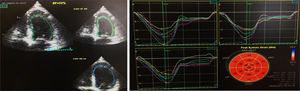

Na primeira avaliação laboratorial venosa realizada foi constatada elevação do nível de troponina I (2,01 ng/mL; normal < 0,02 ng/ml), com um pico máximo de 3,23ng/ml, 12 horas após admissão. O proBNP era de 17316 pg/ml (N < 125). O doente negava dor torácica, atual ou prévia, ou quaisquer sintomas de insuficiência cardíaca. O exame objetivo não demonstrava sinais de patologia cardiovascular, nomeadamente sem sopros ou extrassons à auscultação cardíaca, sem fervores à auscultação pulmonar, sem organomegálias à avaliação abdominal e sem edemas dos membros inferiores. O eletrocardiograma encontrava‐se em taquicardia sinusal (FC 109bpm), com retificação do segmento ST em V5, V6, I e aVL. Um ecocardiograma transtorácico (ETT) foi requisitado, e realizado no dia da admissão, em ecógrafo portátil Vivid I GE, demonstrando um ventrículo esquerdo não dilatado, não hipertrofiado, com um compromisso grave da função sistólica ventricular esquerda, estimada em 26%, devido a hipocinesia difusa; sem doença valvular aórtica ou mitral significativa; ventrículo direito com função sistólica longitudinal conservada, veia cava inferior (VCI) de 17mm, com cinética respiratória mantida e pressão da artéria pulmonar estimada em 28mmHg (Figura 1).